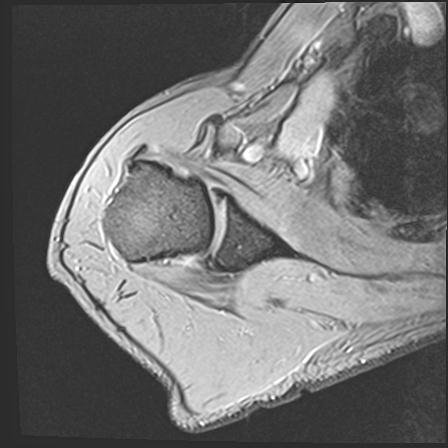

60058 3/9 11/4 右肩 2R+MRI 73歳男性 肩腱板損傷